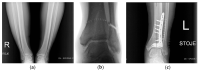

Osteoarthritis is a degenerative condition affecting the whole joint with the underlying bone, representing a major source of pain, disability, and socioeconomic cost worldwide. Age is considered the strongest risk factor, albeit abnormal biomechanics, morphology, congenital abnormality, deformity, malalignment, limb-length discrepancy, lifestyle, and injury may further increase the risk of the development and progression of osteoarthritis as well. Pain and loss of function are the main clinical features that lead to treatment. Although early manifestations of osteoarthritis are amenable to lifestyle modification, adequate pain management, and physical therapy, disease advancement frequently requires surgical treatment. The symptomatic progression of osteoarthritis with radiographical confirmation can be addressed either with arthroscopic interventions, (joint) preservation techniques, or bone fusion procedures, whereas (joint) replacement is preferentially reserved for severe and end-stage disease. The surgical treatment aims at alleviating pain and disability while restoring native biomechanics. Miscellaneous surgical techniques for addressing osteoarthritis exist. Advanced computer-integrated surgical concepts allow for patient personalization and optimization of surgical treatment. The scope of this article is to present an overview of the fundamentals of conventional surgical treatment options for osteoarthritis of the human skeleton, with emphasis on arthroscopy, preservation, arthrodesis, and replacement. Contemporary computer-assisted orthopaedic surgery concepts are further elucidated.